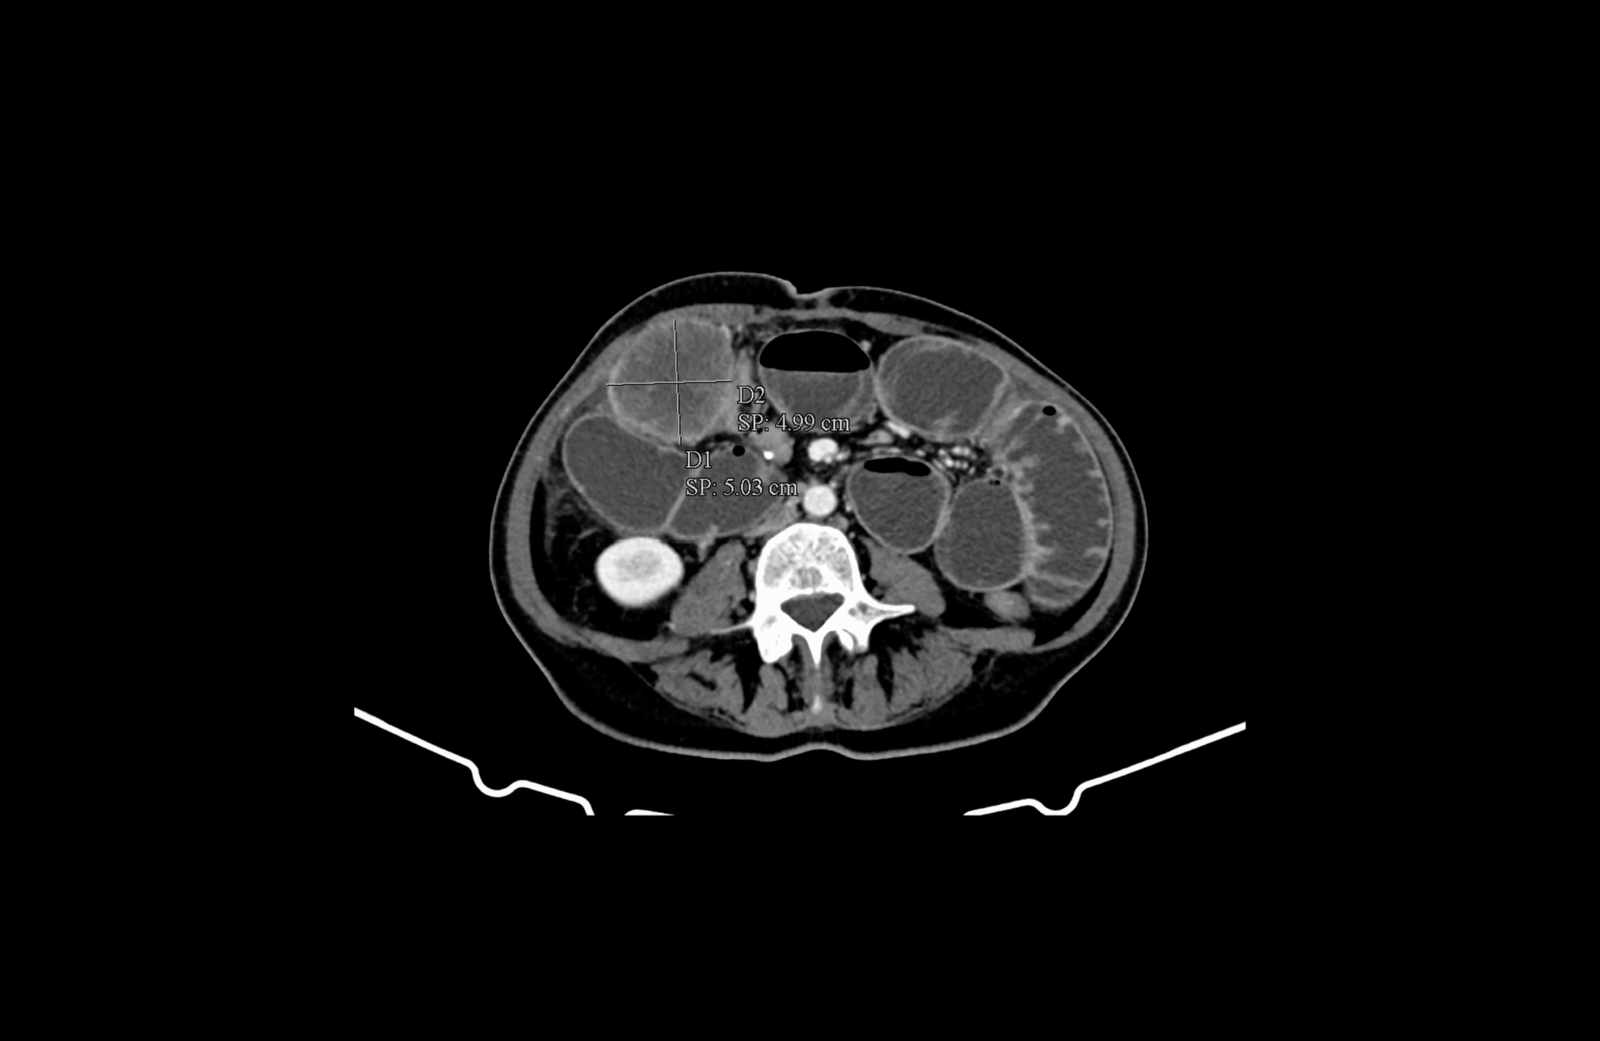

- инфилтрация на мастната бъбречна капсула в дясно

- инфилтрация на предната коремна стена

- инфилтрация на m. psoas major и n. femoralis

Инфилтрация на меките тъкани на предната коремна стена

Инфилтрация на меките тъкани на предната коремна стена и m. iliopsoas, както и прилежащия към него n. femoralis